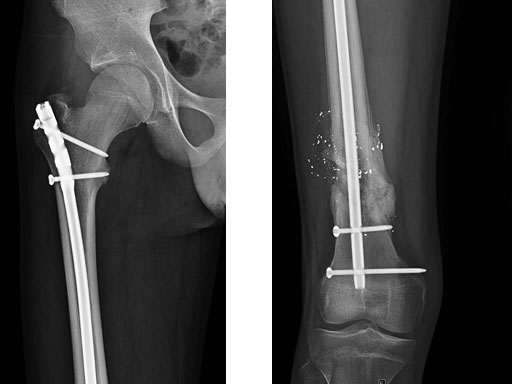

After stabilizing the fracture with an intramedullary nail (Fig 2) the patient was mobilized with weight bearing as tolerated. Uneventful healing and range of motion of the knee and functional ambulation returned to normal. Alignment of the fracture has been maintained with healing and maturation of callus processing as predicted. Blood supply to the proximal femur has been reserved with no signs of avascular necrosis. The ALFN's lateral entry point makes the nail insertion safer and diminishes the risk of circumflex artery injury.

Fig 2 Immediate postoperative AP x-ray.